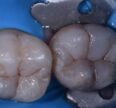

Read MoreDeep caries

Deep caries preserving the marginal ridge of this deep Class I. Caries detector dye and tactile excavation reveals that only stained, affected dentin remains. #KerrSimplishade